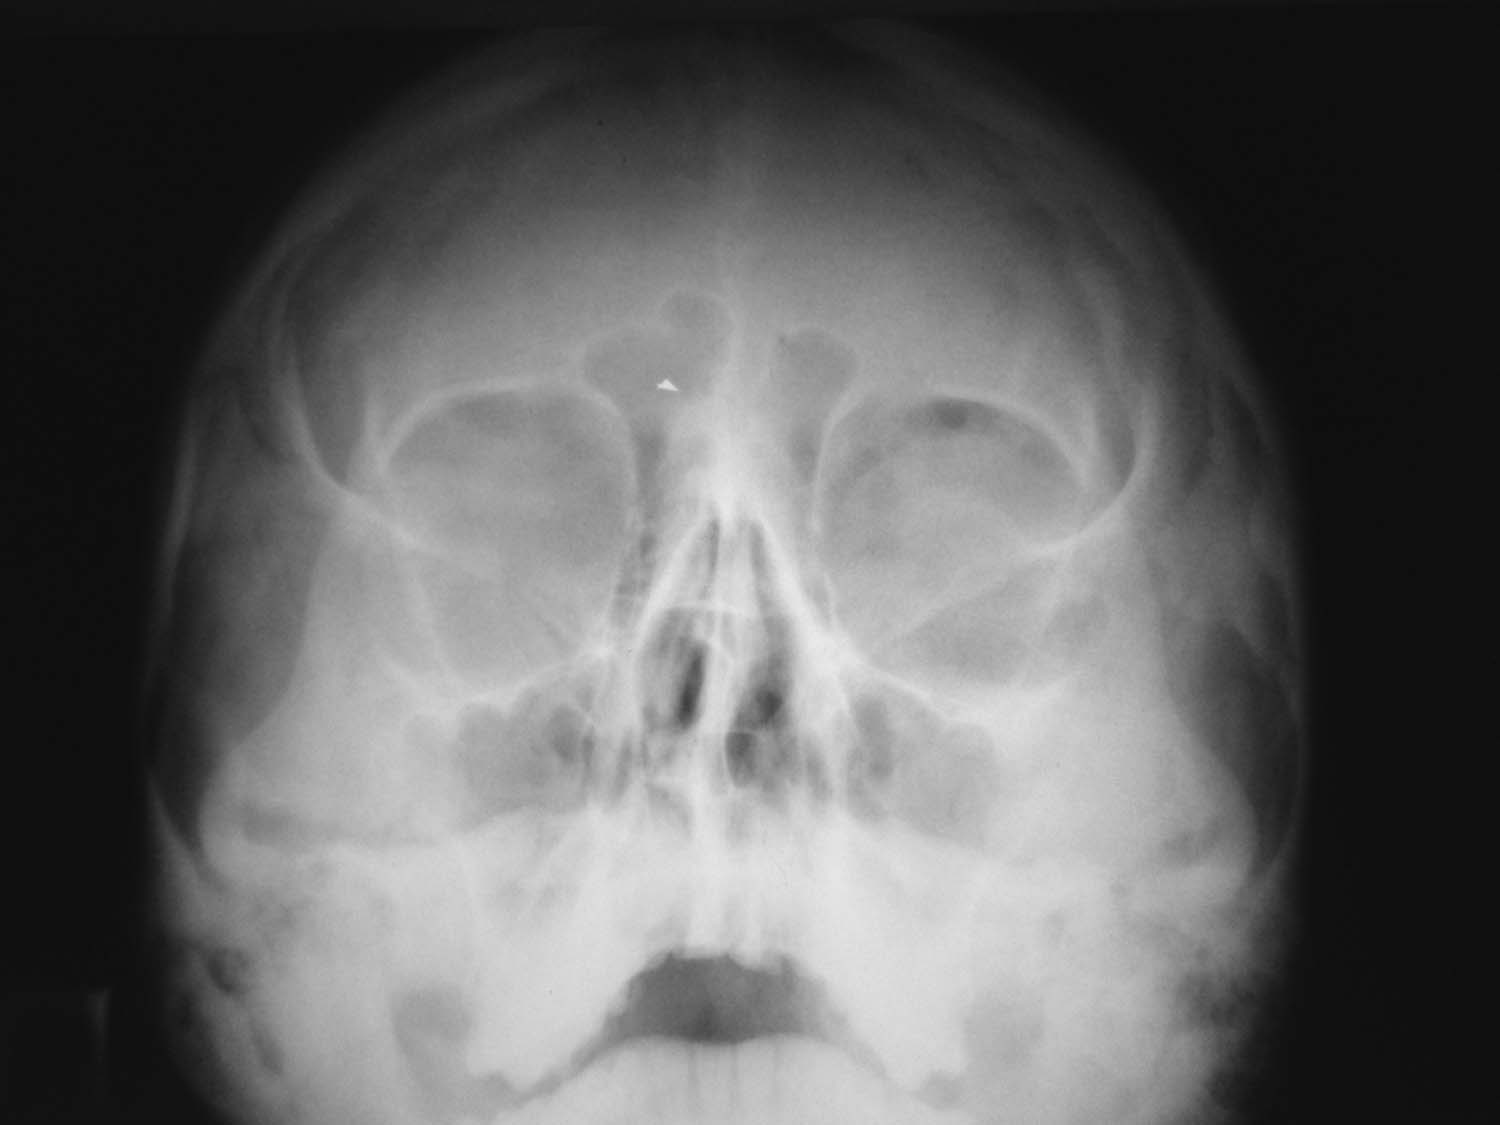

Есть ли интраорбитальная эмфизема?

Женьщина 1983 года рождения, получила удар кулаком в лицо, каторый прошел справа налево, по касательной переносицу, левое глазное яблоко и левую бровь. Внешне слева выраженная параорбитальная гематома. Выполнены рентгенограммы глазниц с интервалом в 2 дня.

Клинически данных за перелом левой глазницы нет. Мне не нравится то что контуры левого глазного яблока такие четкие. Могла ли интраорбитальная эмфизема быть причиной такой четкости контуров глазного яблока? Есть ли она на представленных рентгенограммах? Я подозреваю разрывной перелом стенки левой глазницы, понимаю что КТ может решить этот вопрос, но КТ у нас нет.

Я считаю, что есть.Более выраженная на первом снимке.

А эмфизема слева очень вероятна

Мне кажется, есть. На 1 снимке более выраженная. Воздух, конечно, может быть и под веком, но веко так к носу не уходит.

Эмфизема есть. Вероятнее всего перелом медиальной стенки орбиты. Можно попробовать томограммы, хотя оптимальна КТ.